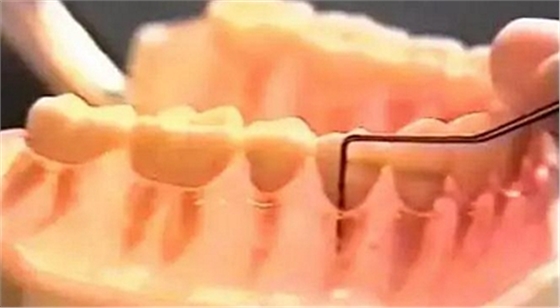

(1)應使用鈍頭帶刻度的牙周探針。

(2)探針須與牙長軸平行,探針的尖端緊貼牙面,探入袋底后記錄從袋底到齦緣的距離(mm),即探診深度。探鄰面時探針緊靠接觸區(qū),尖端可略向鄰面中央傾斜。

(3)探查同一牙面較寬的牙周袋時,應提插式移動,以探明不同深度的牙周袋狀況。

(4)探診時支點要放穩(wěn),用力不可過大,力量掌握在20~25g。